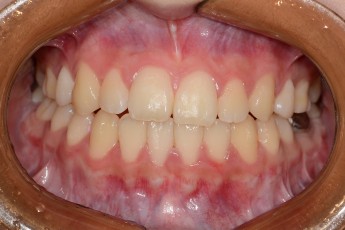

BEFORE & AFTER

- 덧니교정